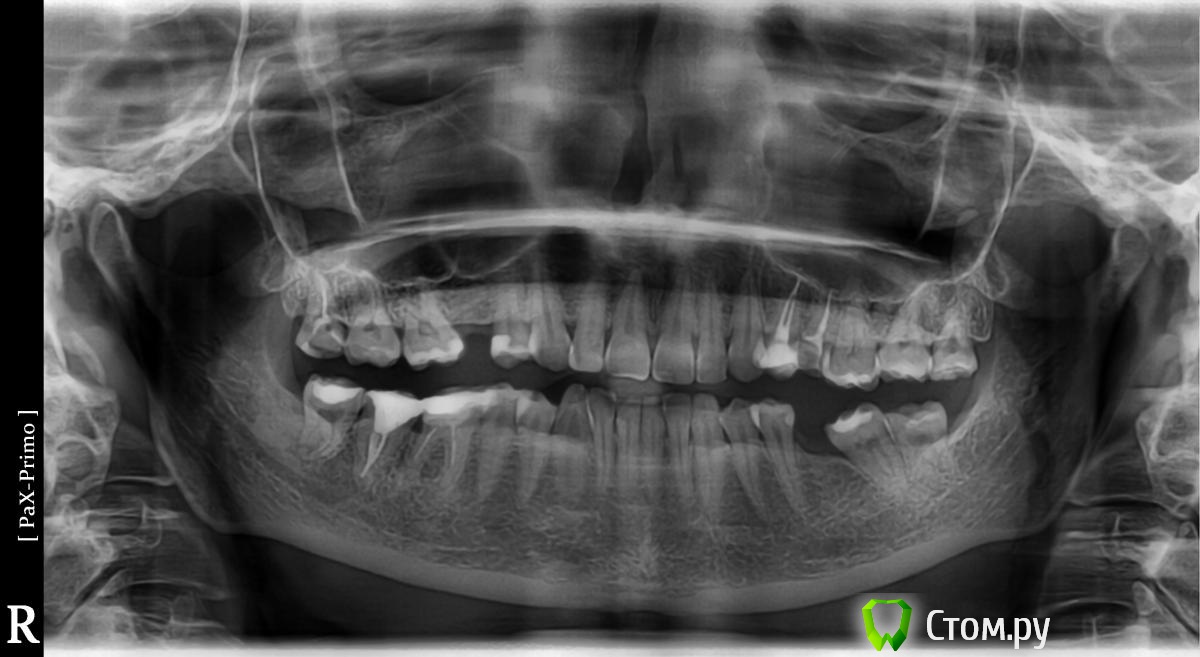

ОПГ и фото прикуса прилагаю.

Была на консультации у гнатолога: по его мнению, это последствие неправильного прикуса, который сформировался из-за проседания и стирания моих пломб ( у меня они стоят на всех жевательных зубах). т.е. высота зубов уменьшилась и нижняя челюсть отодвинулась назад. Решение: ортотик на 3-6 мес, затем полное протезирование...

Затем была на консультации у ортодонта. Он видит причину в раннем удалении 6-ки с левой стороны, получается, что я жую преимущественно на правой стороне, соответственно справа гипертонус мышц и все остальные проблемы. Лечение: удаление всех 8-к, ношение брекетов 1-1,5 года, затем восстановление утраченных зубов.